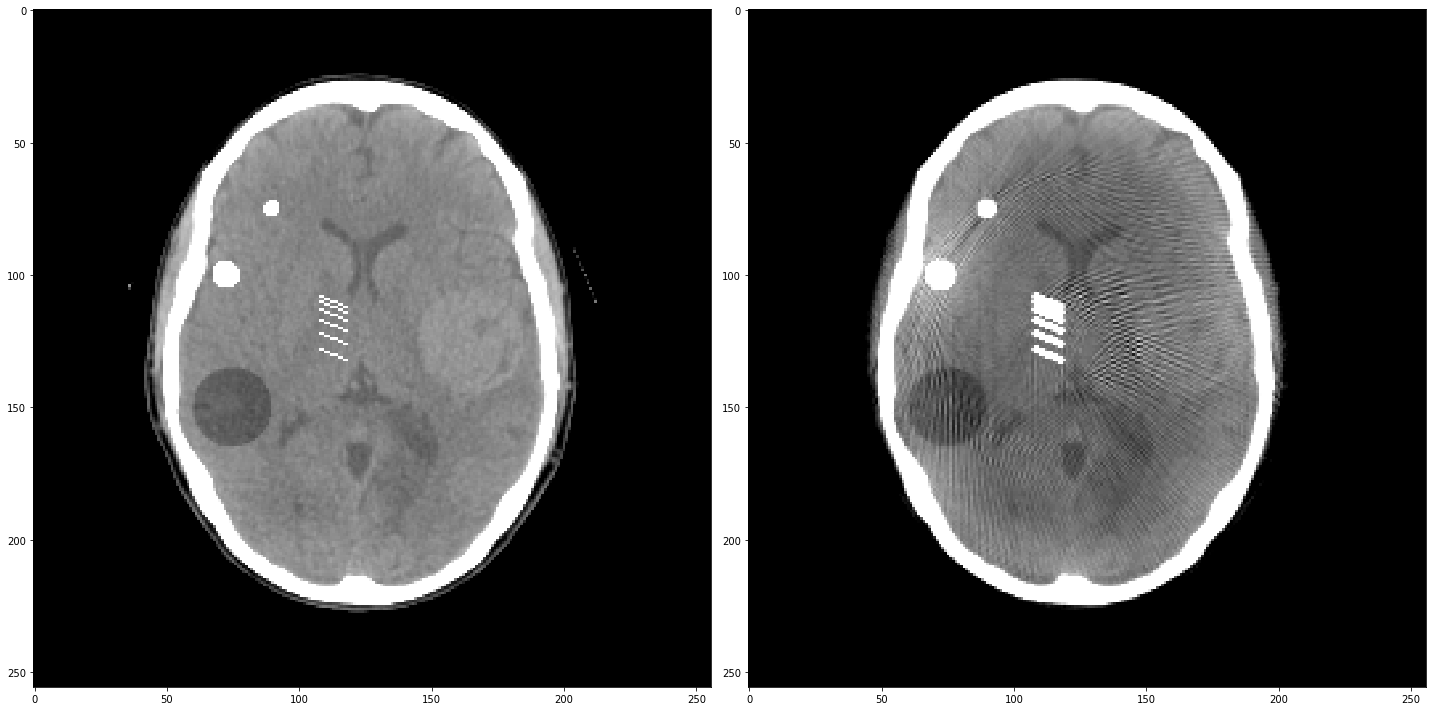

Partie 2 - Non-idéalités du détecteur

Un détecteur présente plusieurs non idéalités ; en premier lieu, il présente des dérives en gains et en offsets. Cela signifie que la mesure faite au niveau d’une cellule du détecteur (un pixel d’un détecteur plan, ou un bin d’un détecteur linéaire), au lieu de mesurer l’intensité $I$ des photons X qui arrivent à la cellule, on mesure \(I_c = \alpha I + \beta.\) $\alpha$ est un gain (proche de 1 généralement), et $\beta$ est un offset. Si on ne fait pas attention à $\alpha$ et $\beta$, on se retrouve avec une projection corrompue $p_c = \log(I_0)-\log(I_c)$.

Chargez l’image ci-dessous, et regardez son sinogramme :

Reconstruisez l’image à partir de ce sinogramme :

1

2

3

4

img_ = iradon(sinogram0, theta=theta, circle=True)

plt.figure(figsize=(10,10))

plt.imshow(img_,**ctDisplay)

plt.colorbar()

<matplotlib.colorbar.Colorbar at 0x7fce56ca4b80>

Questions

- Partant du détecteur utilisé pour le sinogramme précédent (de taille

sinogram.shape[0]), générer un vecteur de gains égaux à 1 et un vecteur d’offsets égaux à 0 (cas idéal). Corrompez le vecteur de gain tous lesnbins par un bruit d’écart-type de 1%. Affichez le vecteur des gains. Générez le sinogramme qui aurait été obtenu si la mesure avait subi ces gains à chaque acquisition. Reconstruisez l’image : qu’observez-vous comme artefacts ? - Corrompez le vecteur d’offsets tous les

nbins (en partant den//2cette fois) par un bruit d’écart-type de 1%. Affichez le vecteur des offsets. Générez le sinogramme qui aurait été obtenu si la mesure avait subi ces gains et ces offsets à chaque acquisition. Reconstruisez l’image : qu’observez-vous comme artefacts ? (FixezI0=10) - Changez la valeur de

I0à 100, 1000, 10000 : qu’observez-vous ? Quels artefacts disparaissent / se maintiennent ? Pourquoi ?

sinogram = sinogram0.copy()

np.random.seed(42)

n = sinogram.shape[0] // 5

# Question 1

# Vecteur de gains

gain = np.ones(sinogram.shape[0])

gain[::n] += np.random.rand() * 0.01

plt.figure()

plt.plot(gain)

plt.show()

# Question 2

# Vecteur d'offsets

offset = np.zeros(sinogram.shape[0])

offset[::n-1] += np.random.rand() * 0.1

plt.plot(offset)

I0 = 10

# Génération du sinogramme corrompu en gains / en offsets / les deux

sinogram = gain.reshape(-1, 1) * sinogram + offset.reshape(-1, 1)

plt.imshow(sinogram.T)

# Reconstruction

out = iradon(sinogram, theta=theta, circle=True)

f,ax = plt.subplots(1,2,figsize=(20,10))

ax[0].imshow(img,**ctDisplay)

ax[1].imshow(out,**ctDisplay)

plt.tight_layout()